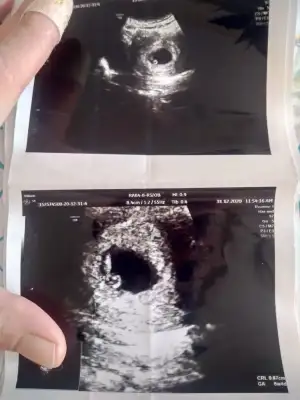

Kiz sankiCanım bana da bir tahminde bulunabilirmisin vajinal ultrason teşekkür ederim

Arkadaşlar cinsiyet tahmininde bulunablir misiniz vajinal ultrasonda çekildi